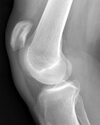

what is this finding called? association?

Segund fx

bony aculsion of anterolateral ligament

pathognominic for acl tear

associated with acl tear 75-100 percent of the time.